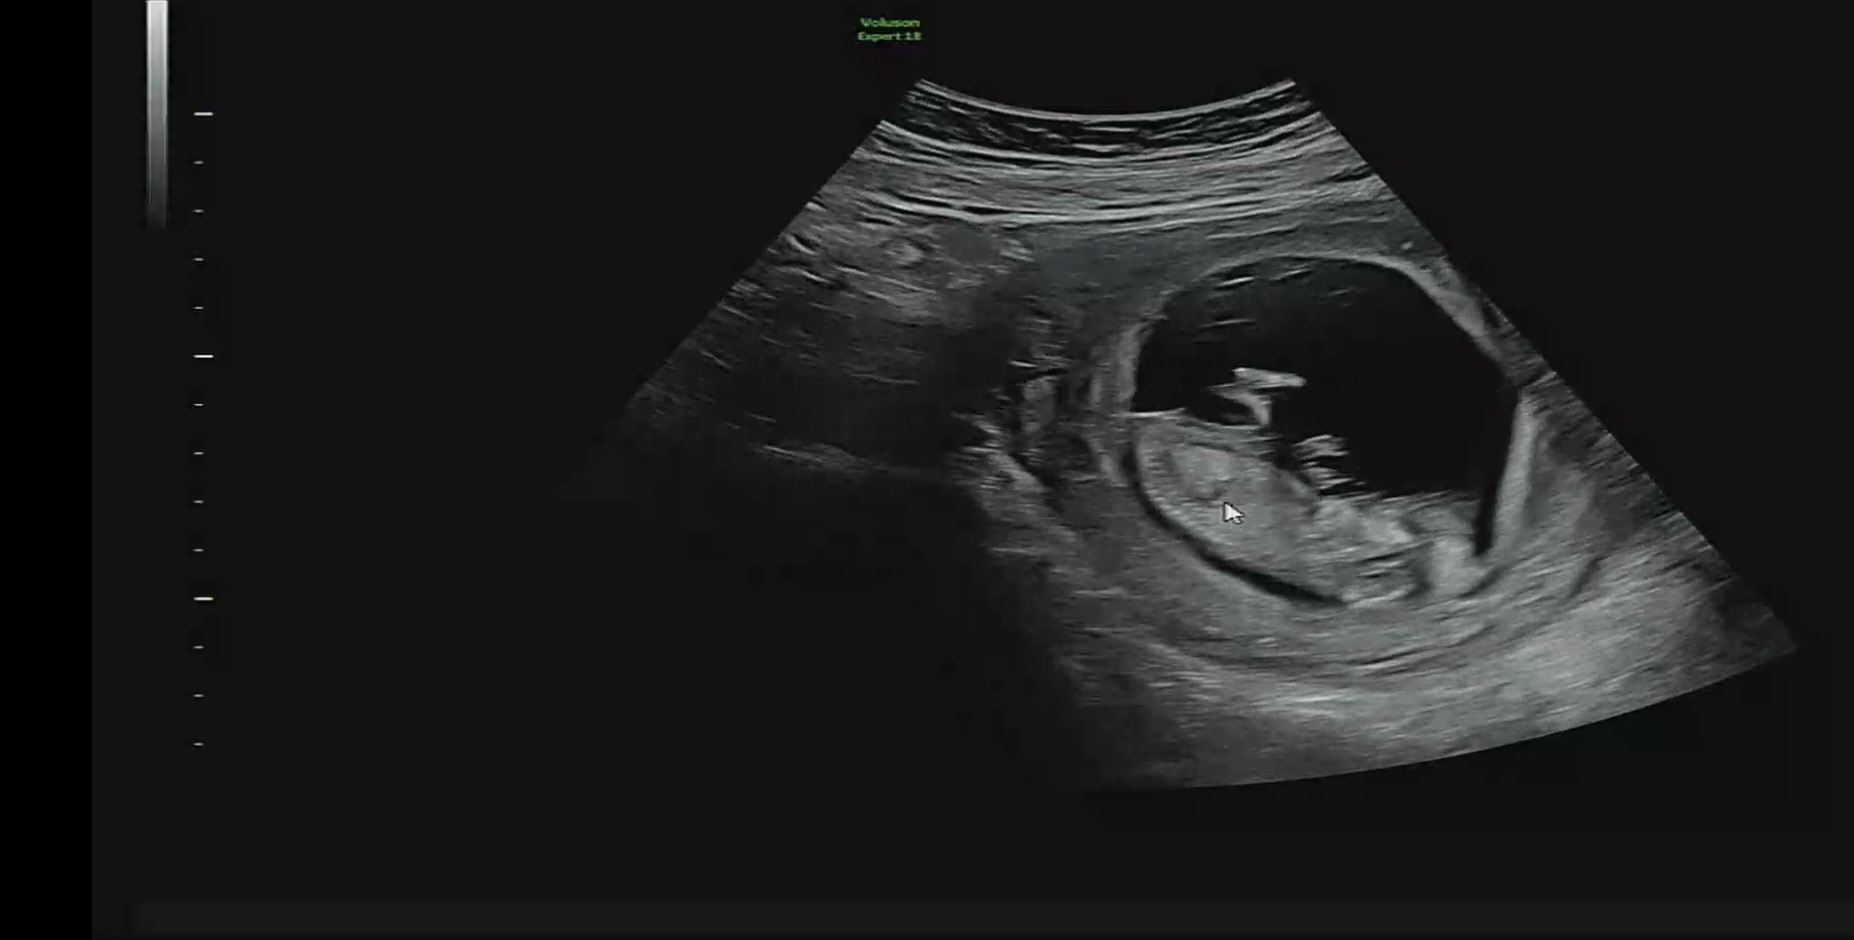

오늘 12주차 니프티검사하고 왔습니다 혹시 이자신으로도 각도법 가능 할까요?